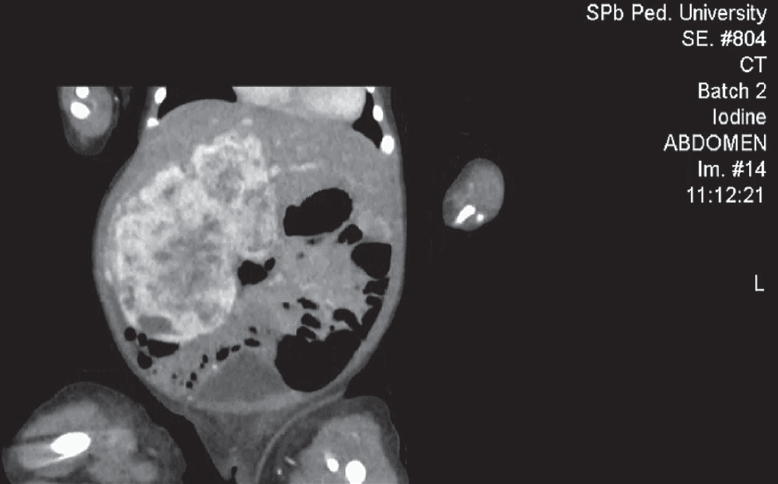

Гемангиомы — наиболее часто встречающиеся доброкачественные сосудистые образования печени детского возраста, которые могут приобретать как злокачественное течение, так и спонтанно регрессировать. На первом году жизни их распространенность составляет 10–12 %. Среди недоношенных детей распространенность гемангиом коррелирует со степенью недоношенности. Гемангиомы небольших размеров, как правило, не требуют специфического лечения и протекают бессимптомно. Образования крупных размеров могут вызывать жизнеугрожающие состояния: тяжелую тромбоцитопению с коагулопатией (синдром Казабаха – Меррита), анемию, кровоизлияние в опухоль, спонтанные и травматические разрывы опухоли, сердечную недостаточность, связанную с внутриопухолевым шунтированием кровотока, синдром абдоминальной компрессии, тяжелый гипотиреоз. Диагноз устанавливается на основании совокупности данных медицинской визуализации, лабораторной диагностики и клинической картины. В данном обзоре представлены ключевые моменты общей классификации, наиболее характерные диагностические признаки, а также базовые алгоритмы лечения гемангиом печени у новорожденных и детей первого года жизни. Также описаны 2 клинических случая новорожденных с гигантскими гемангиомами печени, которые обследовались и получали лечение в отделении патологии новорожденных и детей грудного возраста Перинатального центра Санкт-Петербургского государственного педиатрического медицинского университета с описанием особенностей течения каждого из них.